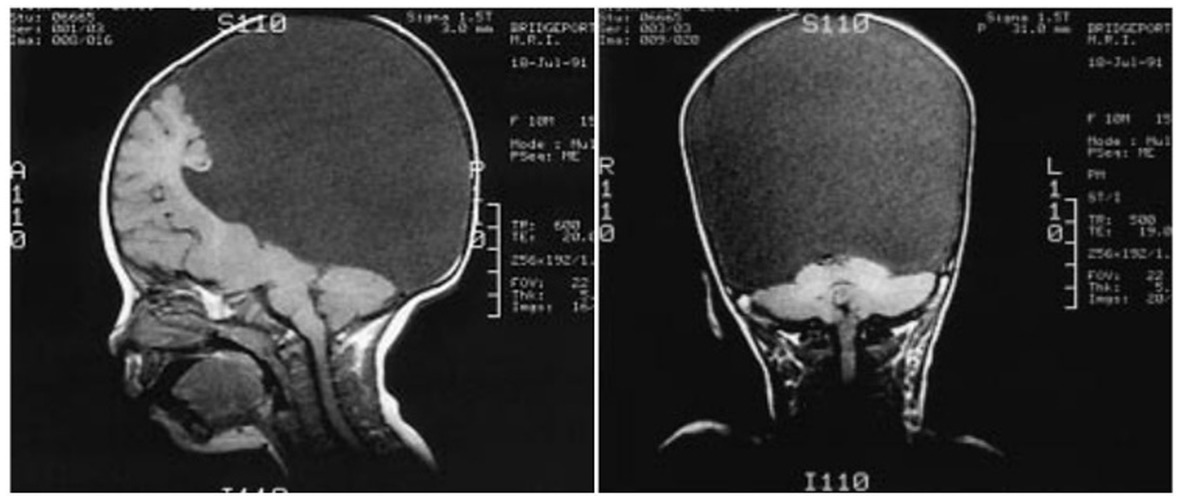

Nevertheless, only one case showing the contrary should be sufficient to disprove a universal rule. Four such cases were brought to light in 1999 by a group led by Shewmon et al. (1999). They studied the states of awareness in congenitally decorticate children–that is, the cases of four children who were almost completely lacking cortical tissue and were neurologically certified as being in a vegetative state. Yet, the loving care of their mothers (or of someone who adopted them and bonded with them via dedicated full-time caring) could gradually ‘awaken’ in them a conscious awareness. From an initially unresponsive state, they showed clear signs of having developed auditory perception and visual awareness (despite the total absence of the occipital lobe that, in normal conditions, hosts the visual areas). For example, they tracked faces and toys, looked at persons they recognized, could distinguish between their mothers or caretakers, listened to music for which they manifested preferences with their facial expressions, including smiling and crying, and, at least in one case, gave clear indications of self-recognition in a mirror. Shewmoon notes: “Were they [the decorticate children] not humans studied by clinicians but rather animals studied by ethologists, no one would object to attributing to them ‘consciousness’ (or ability to ‘experience’ pain or suffering) based on their evident adaptive interaction with the environment.”

One can still point out that the children were not completely decorticated, as some cortical tissue was still left. Figure 6 shows that a remnant of the frontal lobe is still present, possibly producing the conscious awareness. But that neural mechanisms of conscious function cannot be confined to the cerebral cortex alone is becoming much more plausible (Merker, 2007).

Figure 6

Congenitally decorticate children MRI brain scan (midline sagittal and posterior coronal plane). Credit: Shewmon et al. (1999). Reproduced with permission from Wiley.